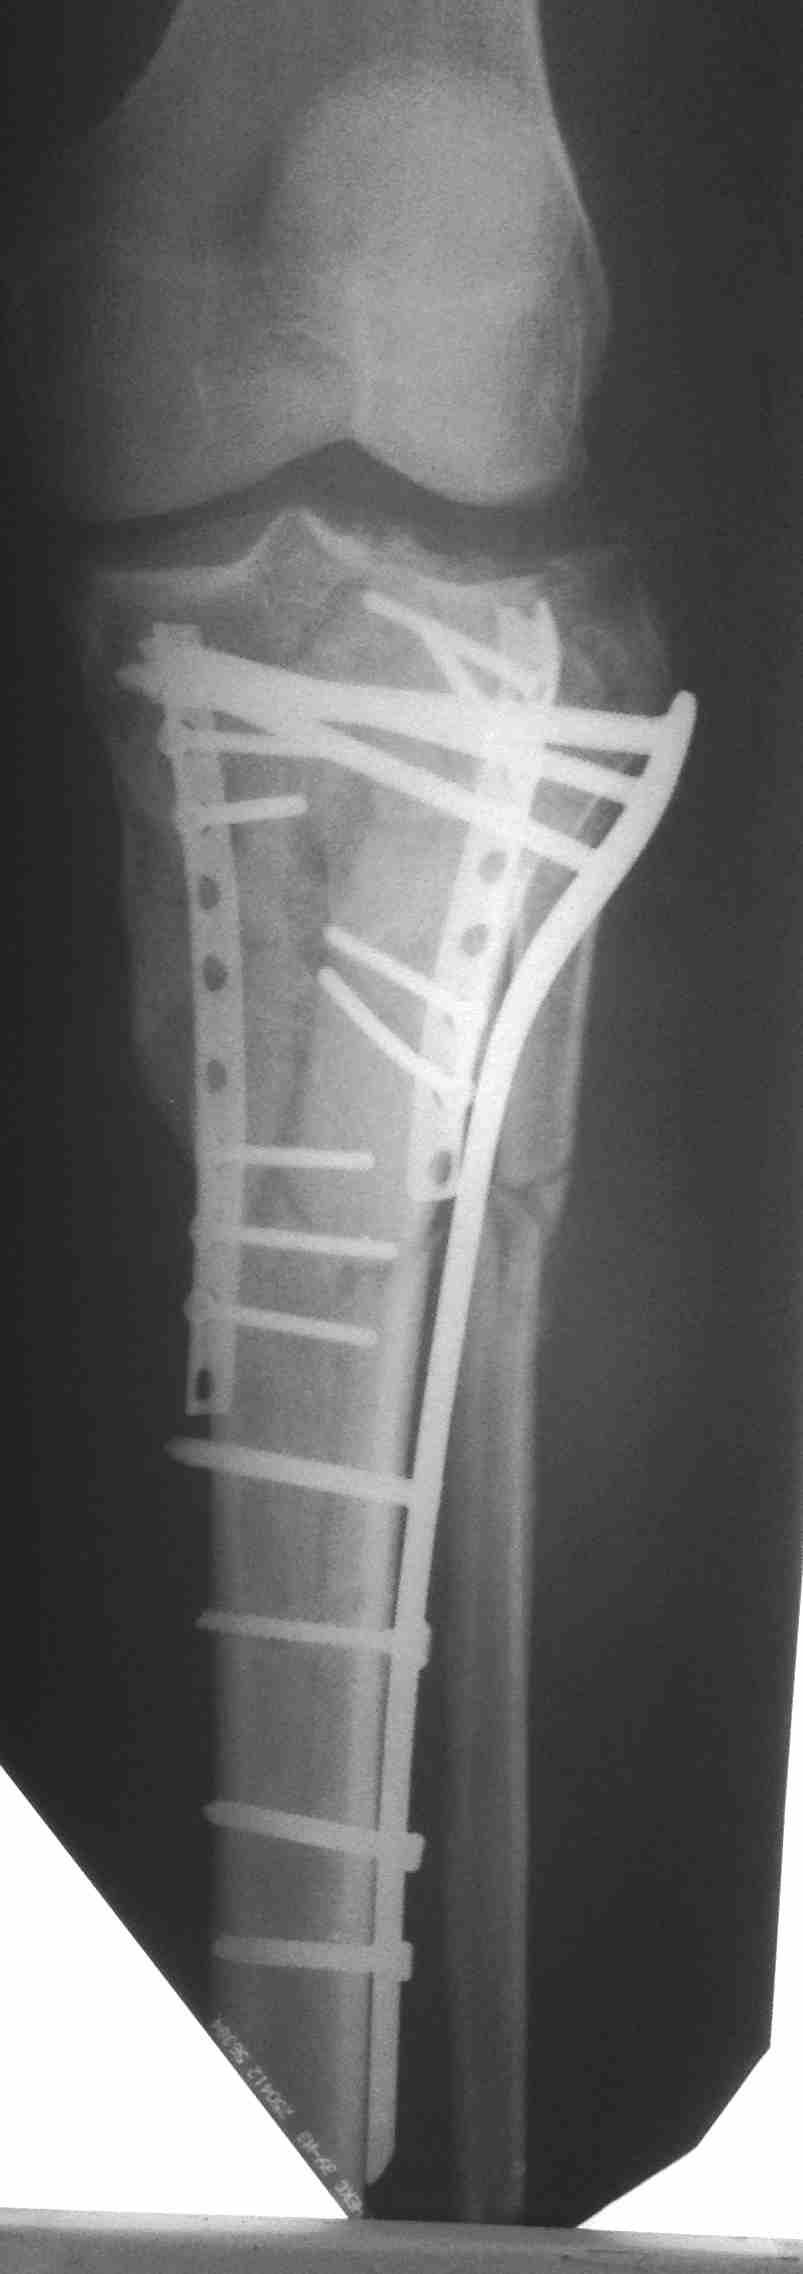

[Ortho] перелом мыщелков голени и вывих бедра (результат операции)

продолжение темы http://weborto.net/forum/1435828753/

Кожа пришла в норму только к полутора месяцам, операция из двух доступов.